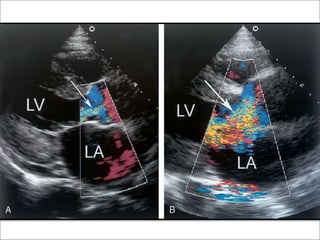

• 4.COLOR DOPPLER--- JET WIDTH ,JET AREA,VENA

Color flow mapping

• Most commonly used one to assess the severity.

• Sensitivity of greater than 95% and a specificity of nearly

100% for establishing the diagnosis.

Height of AR jet

• From parasternal long axis view – the height of the jet just below

the valve can be measured using electronic calipers.

• Dimension expressed as the percentage of LVOT dimension to

provide an estimate of severity.

Jet height/outflow tract dimension ratio.

• Greater the percentage – the more severe the regurgitation.

• A jet that occupies more than 60% of the LVOT(either height or

area)usually indicates severe AR.

• Short axis view at the level of great arteries – area of jet compared

to aortic orifice.